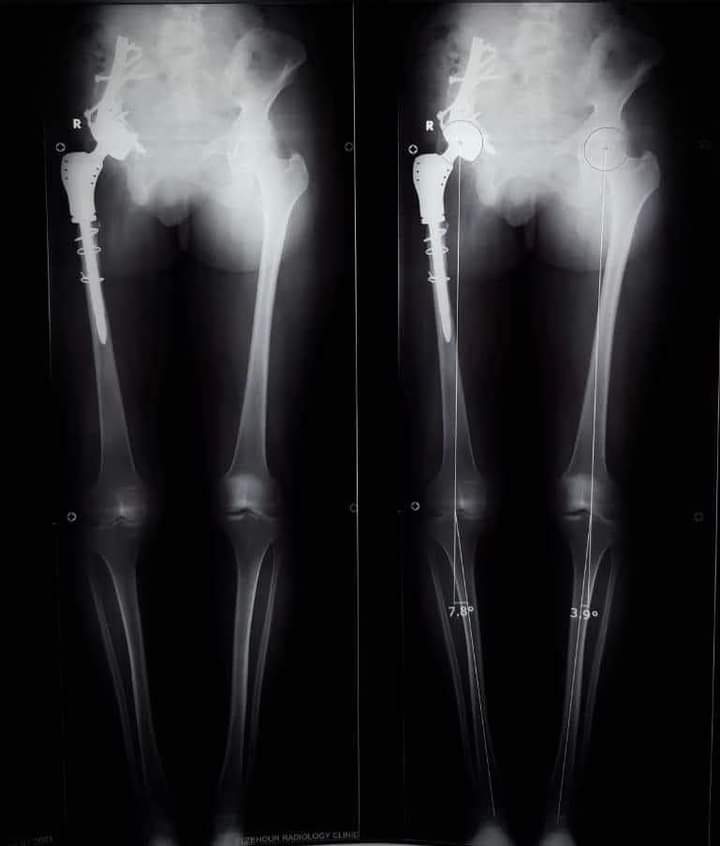

وأوضح الدكتور عمرو السيد علي أستاذ جراحة العظام، واستشاري الجراحات الميكروسكوبية بجامعة أسيوط ، أن المريضة تبلغ من العمر 15 عامًا ، وكانت تعاني من وجود ورم في عظمة الآلية، ومفصل الحوض؛ مشيرًا إلى إجراء العملية الجراحية على مرحلتين في إطار زمني 3 شهور ؛ لتجنب البتر؛ حيث تم في المرحلة الأولي إزالة الورم من عظمة الآلية، ونقل الجزء العلوي من عظمة الفخذ ؛ لتحل محل عظمة الآلية.

وأوضح الدكتور محمد مهران أستاذ جراحة العظام المساعد، واستشاري جراحات تغيير المفاصل الصناعية بجامعة أسيوط، أنه تم- بعد إجراء الفحوصات الطبية- تركيب مفصل صناعي كامل ذي مواصفات خاصة للحوض، وذلك دون اللجوء لتثبيت المفصل، ولتجنب البتر لهذا الطرف؛ مشيرًا إلى نجاح العملية، واستقرار الحالة الصحية للمريضة، وتمت متابعتها؛ لحين عودة حركة المريضة لصورتها الطبيعية، ومشيرا في الوقت نفسه، أنه تم نشر العملية الجراحية عالميًا: في مجلة علمية متخصصة للحالات الصعبة؛ بمساعدة الدكتور أحمد عادل خليفة مدرس جراحة العظام بكلية طب قنا- جامعة جنوب الوادي.